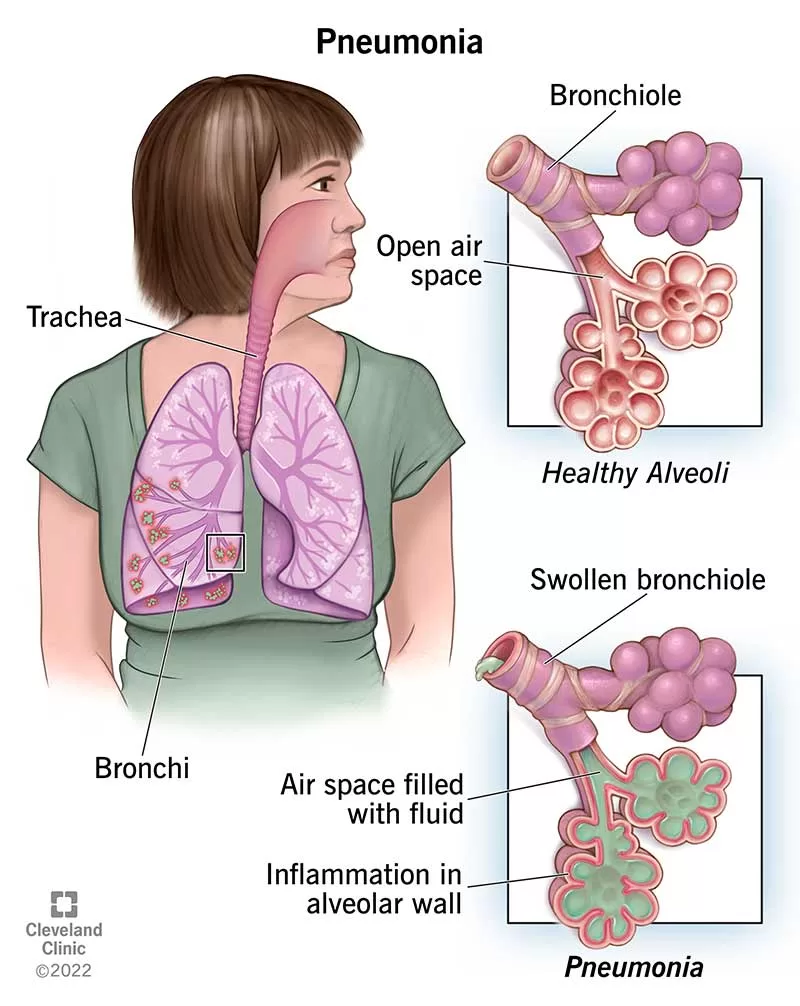

5. Pneumonia

Pneumonia adalah peradangan paru-paru dimana alveolus biasanya terinfeksi oleh cairan dan eritrosit berlebihan. Infeksi disebarkan oleh bakteri dari satu alveolus ke alveolus lain hingga dapat meluas ke seluruh lobus bahkan seluruh paru-paru. Umumnya disebabkan oleh bakteri Streptococcus, Diplococcus pneumoniae, dan bakteri Mycoplasma pneumoniae.